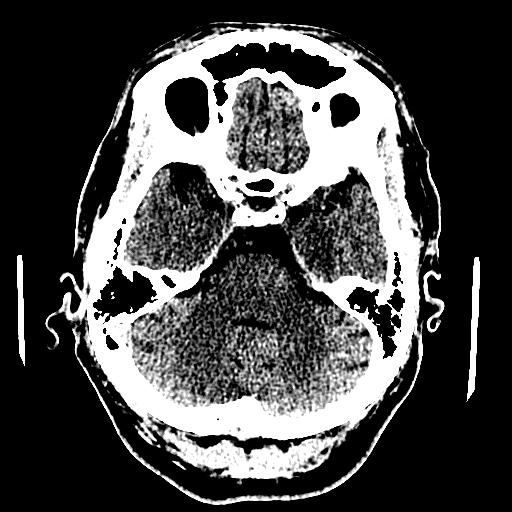

| Left anterior SDH |

![]() |

| Longitudinal petrous bone fracture, with opacification of the mastoid air cells, and pneumocephalus. |